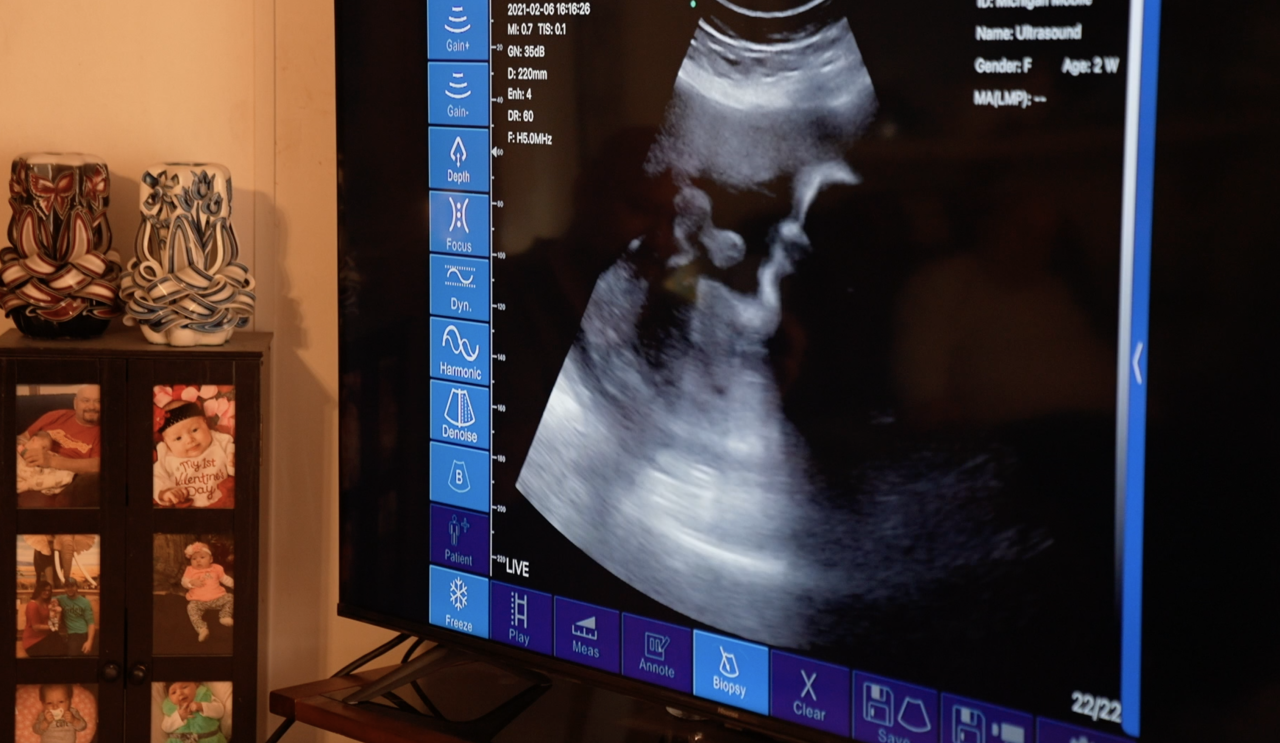

Darrin and Linda Hurley listened to their baby girl's heartbeat together and with their close family members on Saturday thanks to Michigan Mobile Ultrasound.

Brittani McDaniels, the owner of Michigan Mobile Ultrasound, has been a registered sonographer for more than ten years. She started doing in-home visits in November. She's done 15 so far.

Linda said seeing the baby on the big screen, surrounded by family, meant a lot.